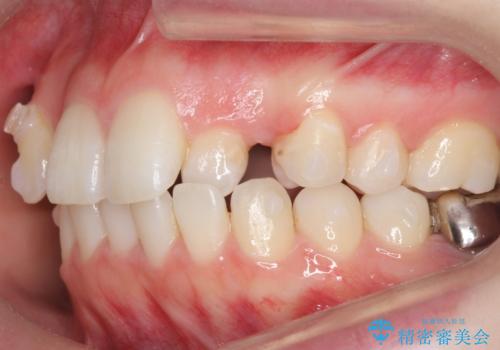

- 前歯のがたつきを主訴に来院。

左上の犬歯が歯肉退縮しており、そこを抜歯して矯正することにしました。

右上については、奥歯をインプラント矯正により後ろに動かして、引っ込んだ前歯を並べるスペースを確保しました。

右下6番については保存不可能であり、矯正治療終了後にインプラント補綴しています。